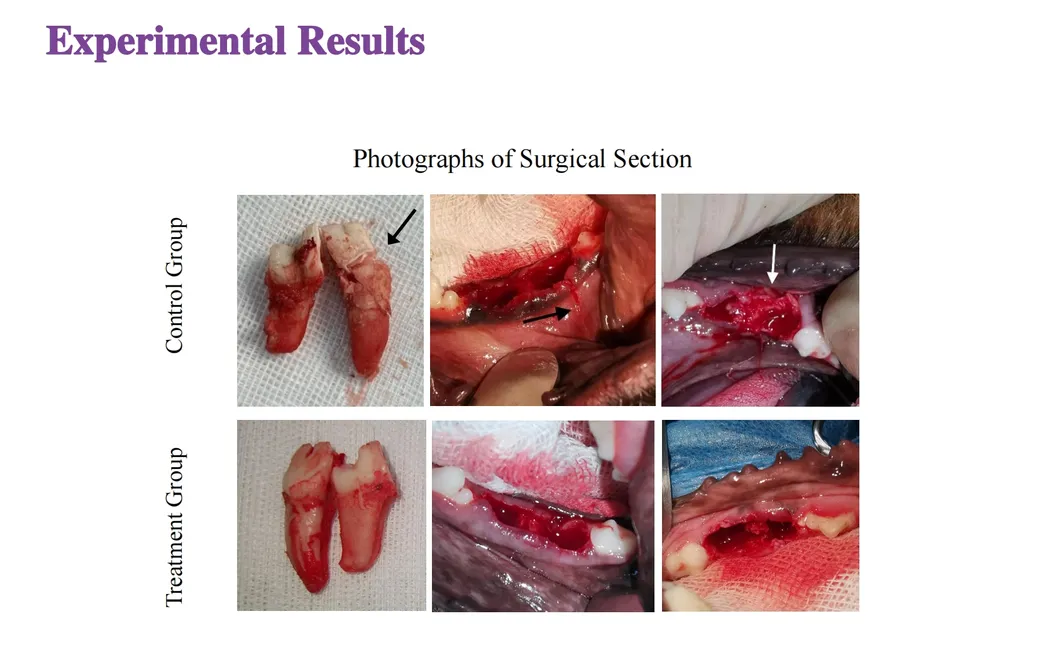

This study evaluated the effectiveness of state-of-the-art dental tools for veterinary use. The treatment group utilized the revolutionary Pneumatic Dental Elevator Kit. Critical factors observed included physiological parameters, intraoperative complications, extraction duration, and socket damage. Rigorous statistical analysis highlights the superior performance of these advanced tools.